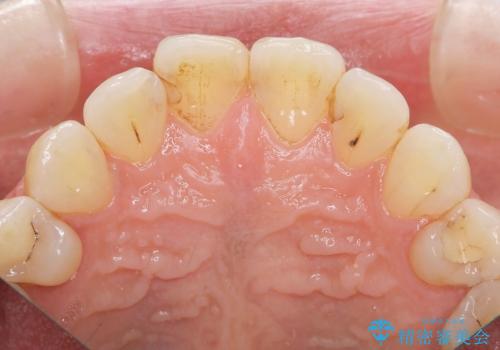

- 数年前に前歯の虫歯治療し、コンポジットレジン修復がなされてい箇所の審美障害の改善を希望され来院されました。

再度レジン修復を行うか、劣化のスピードは遅いが歯の削合が必要なセラミッククラウンの治療の選択肢をご提案し、今後のやりかえの心配の少ないセラミッククラウン治療を希望されました。